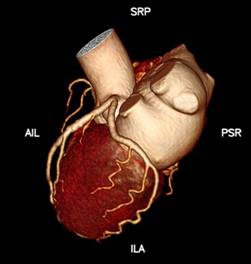

1、心脏检查时无需屏气,无需服药控制心率

Apex CT拥有160mm超宽体探测器,旋转一周仅需0.28s,即可以在一个心动周期内完成整个心脏的扫描。患者无需提早一小时来服药控制心率,高心率、房颤室颤、无法配合呼吸的患者都能在自然状态下接受检查,并通过高能量子球管使用的低kV高mA的扫描模式,在降低对比剂速率、用量和辐射剂量的同时,还能提高组织对比度,得到更高的密度分辨率,显示出更清晰的病灶。